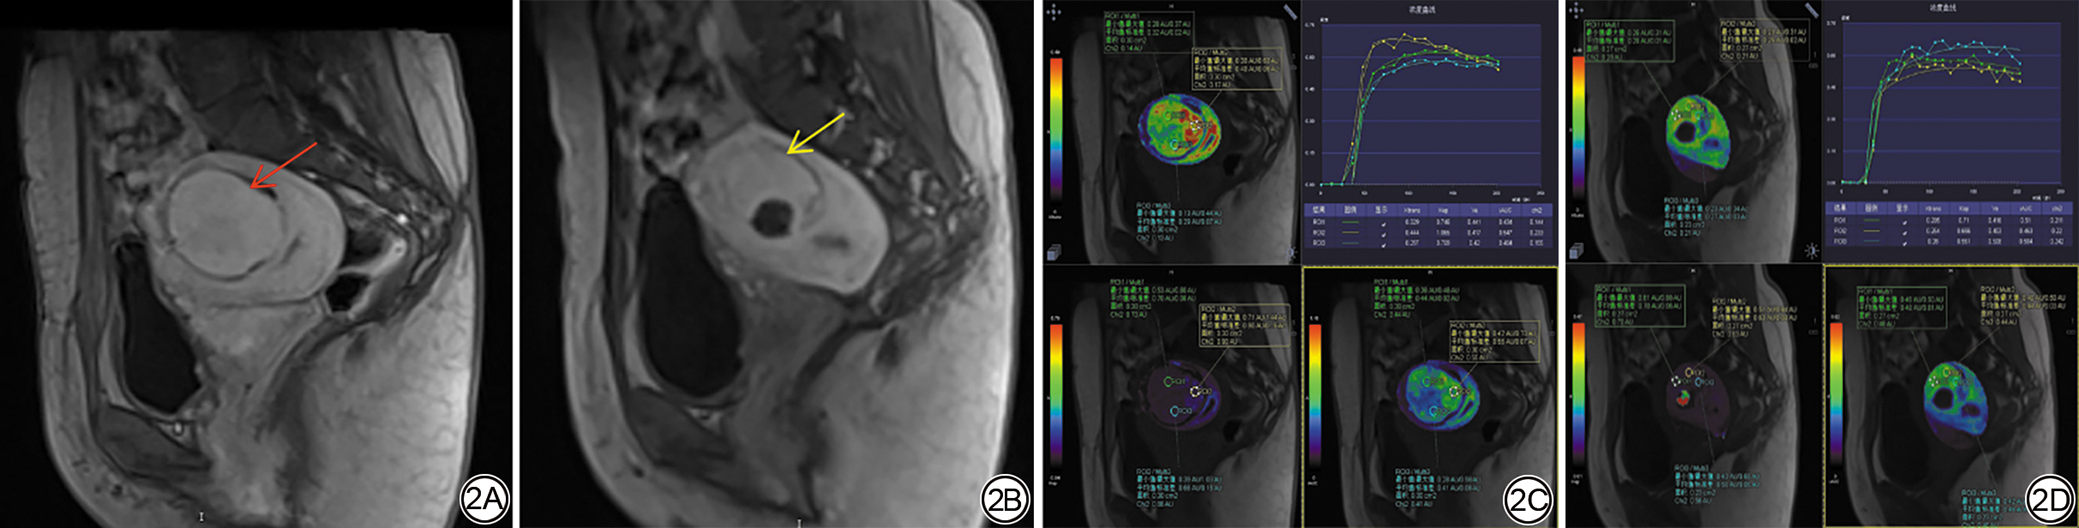

本研究共纳入116例子宫肌瘤患者,其中非充分消融组55例,充分消融组61例。皮下脂肪厚度、子宫肌瘤的T2信号强度值和DCE信号强度值测量如图1。对两组间的基线特征进行比较发现,非充分消融组的皮下脂肪厚度高于充分消融组,差异具有统计学意义(P<0.05)。两组在DCE信号强度值、子宫肌瘤复生长的病例数等临床特征方面差异均有统计学意义(P<0.05),详见表2。两组间子宫肌瘤体积、T2WI上肌瘤/腹直肌信号强度(signal intensity, SI)、DCE-MRI参数iAUC值差异具有统计学意义(P<0.05),详见表3

图1  女,35岁,子宫肌瘤患者。轴向T2WI图示皮下脂肪厚度(1A;红箭)和子宫肌瘤(1B;黄箭)及肌肉(1B;白箭)的T2信号强度,矢状面动态对比增强(DCE)MRI图示子宫肌瘤(1C;黄箭)和子宫肌层(1C;白箭)的对比增强信号强度。

Fig. 1  A 35-year-old female patient diagnosed with uterine fibroid. The axial T2WI shows subcutaneous fat thickness (1A; red arrow) and T2 signal intensity value of uterine fibroid (1B; yellow arrow) and muscle (1B; white arrow), sagittal view of T1WI dynamic contrast-enhanced MR image shows contrast-enhance signal intensity value of uterine fibroid (1C; yellow arrow) and the myometrium (1C; white arrow).